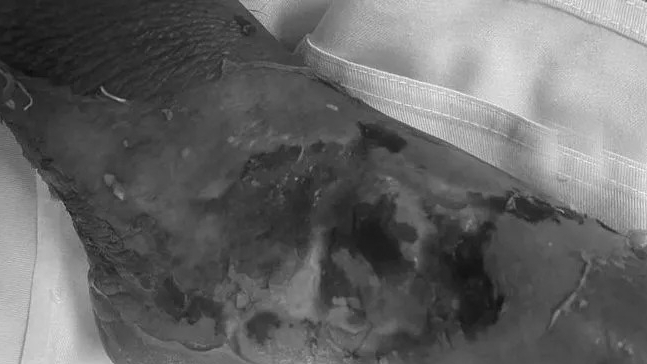

Các bác sĩ đã mở đường ngục trước bên liên sườn IV trái vào khoang màng phổi có dịch đục, vào trung thất trước bóc tách vào ổ áp xe trung thất trước có nhiều dịch mủ đục, hôi thối, rửa sạch. Mở màng ngoài tim có nhiều dịch mủ, rửa sạch, đặt 2 ống dẫn lưu màng phổi trái và 2 ống dẫn lưu màng phổi phải theo dõi, đồng thời chăm sóc bơm rửa khoang màng phổi liên tục